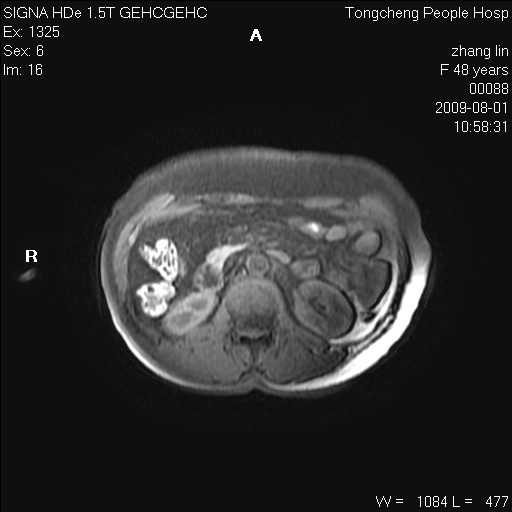

女,48岁。健康体检,彩超发现右肾占位性病变。平素健康。

临床诊断:右肾占位性病变,性质待定(囊肿?肿瘤?)。

上中腹部mr平扫+增强扫描,图像如下:

右肾上极见一类圆形病灶,t1wi呈等信号t2wi呈等高混杂信号,三期增强无强化,边界清---考虑囊肿出血。

同反相位均表现为等信号,病变无强化,考虑含蛋白的囊肿可能,弥散加权相或许有些帮助,

慢性胆囊炎